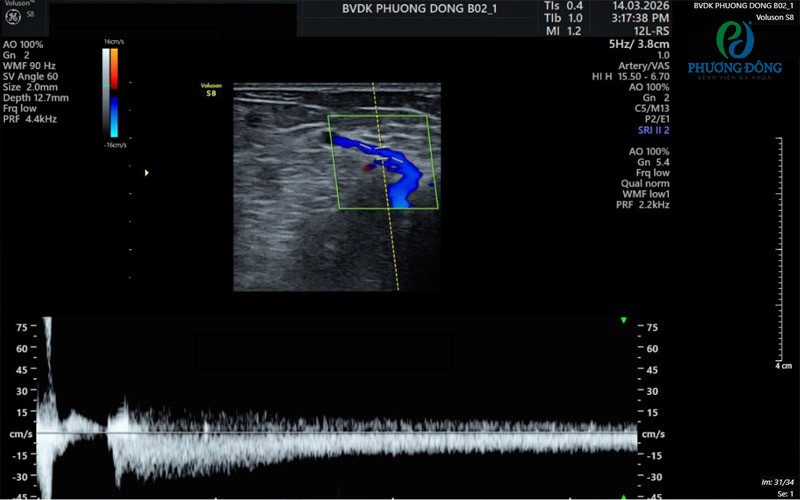

Bệnh nhân có dòng trào ngược kéo dài trong bệnh cảnh suy van tĩnh mạch chi dướiBệnh nhân có dòng trào ngược kéo dài trong bệnh cảnh suy van tĩnh mạch chi dưới

• Doppler màu: hiển thị dòng máu bằng màu sắc

• Doppler xung: đo vận tốc dòng máu tại một điểm

• Doppler liên tục : đo vận tốc dòng máu bằng sóng siêu âm liên tục

• Duplex Doppler: kết hợp siêu âm 2D và Doppler

Tại bệnh viện đa khoa Phương Đông đã được đầu tư rất nhiều máu siêu âm hiện đại như : Philips Affiniti 70, Voluson S8 , Voluson P8……. với độ phân giải cao sẽ cho ra hình ảnh sắc nét , đo tốc độ dòng chảy chính xác sẽ giúp cho các bác sĩ đánh giá đúng tình trạng mà người bệnh gặp phải.